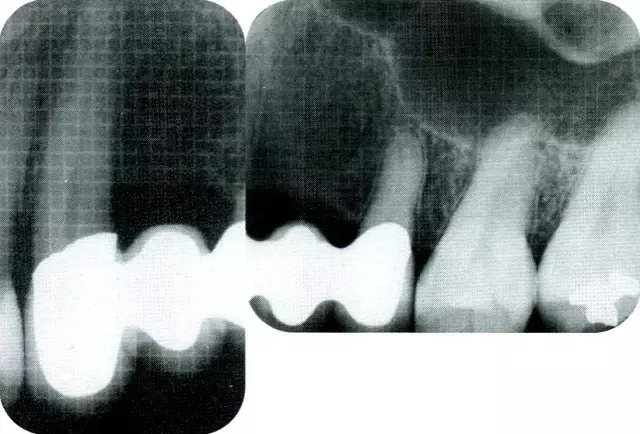

▲圖9-2  術(shù)前x片。

▲圖9-4  術(shù)前的x片。